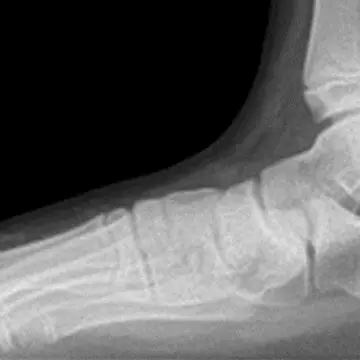

「プレミアムプランでは、靴を履いた状態でのレントゲン検査も行っています。ふだんよく履く靴や、お気に入りだけれど痛い靴などをお持ちいただいて検査します。着用したとき、足元の骨格がいったいどのようになっているのかが一目瞭然です。必要に応じて提携している義肢装具士からの靴のアドバイスを受けたり、適した靴やインソールをオーダーメイドすることも可能です」(久道先生)